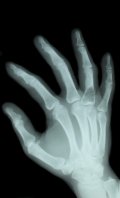

Откуда этот треск в суставах?

Типичный вид соединения суставов в человеческом организме - фаланги пальцев и плечи. В них две кости смыкаются в капсулу, которая носит название соединительной, или суставной. Внутри нее - увлажняющее вещество, именуемое синовиальной жидкостью, в нем - разжиженный газ. Растягивая связку, мы фактически сжимаем капсулу вместе с ее содержимым. В результате, богатые азотом газы покидают синовиальную жидкость. Выход их сопровождается подобием щелчка. После того как летучие вещества (газы) покинули увлажнитель, сустав становится более подвижным, связки - гибче. И вот мы уже делаем новые успехи в йоге.

Наверняка все обратили внимание, что нельзя дважды подряд щелкнуть одним суставом. Чтобы услышать характерный «чпок» повторно, придется подождать, пока жидкость в капсуле вновь наполнится газами. А на это потребуется 15-30 минут. Если привыкли разминать пальцы, снимая напряжение, попробуйте вместо этого дышать глубже или пройтись в быстром темпе. Поскольку "хруст" пальцев хоть и не приведет к артриту, но может ослабить хватку. В буквальном смысле.